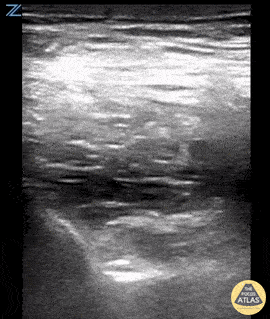

A PENG block was performed using the linear probe. The hyperechoic psoas tendon can be seen lifting off the ileum with the injection of anesthetic. Ariella Cohen M.D., Eric Quinn M.D.